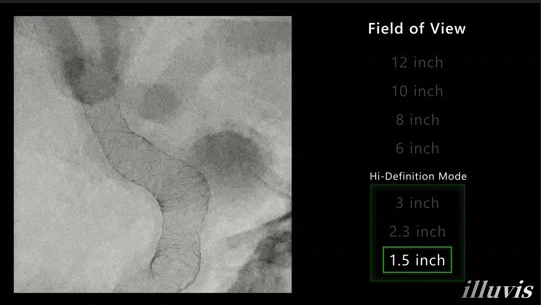

在神经、心脏及外周介入中,医生常面临“看不清”的困扰,如支架太细、血管太密、造影剂过亮,导致判断误差。有时需要反复造影和调整,不仅延长手术时间,也增加辐射与造影剂用量。Sky+搭载76μm显微高清大平板探测器,在更大视野下呈现微至金属丝级的细节结构,让医生看得见,也看得准。

(显微高清模式下,颅内密网支架的实时透视影像)

以神经介入为例,在对颅内密网支架进行细节成像时,不同于传统数字放大产生的“伪清晰”,Sky+ 采用物理光学放大技术,在保持原生分辨率的同时实现从全景到显微的无损切换。显微高清模式(1.5 英寸真实光学视野)可在传统 6 英寸画面基础上清晰呈现支架金属丝结构与血管边界,使医生在透视下即可实时判断支架展开与贴壁情况,精准把握术中状态。